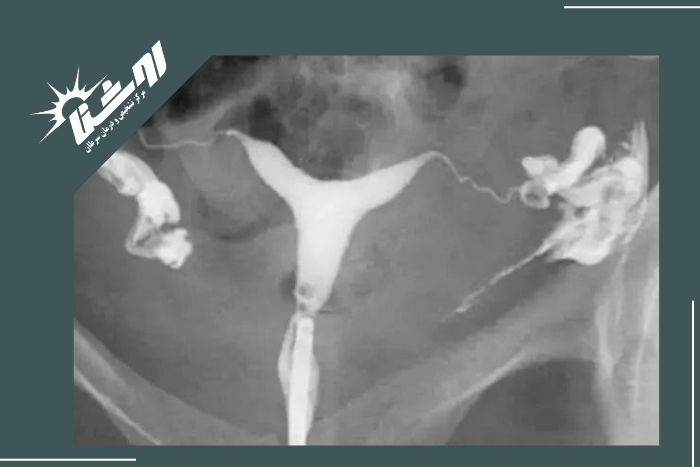

بهترین زمان برای انجام عکس رنگی رحم معمولاً بین روزهای هفتم تا دهم سیکل قاعدگی است. در این بازه رحم از خونریزی پاک شده و احتمال بارداری وجود ندارد بنابراین نتیجه دقیقتر خواهد بود. البته زمان دقیق انجام این بررسی را پزشک شما مشخص میکند چون ممکن است بر اساس شرایط بدنی و نوع سیکل قاعدگی زمان مناسب کمی متفاوت باشد.مشاوره با پزشک